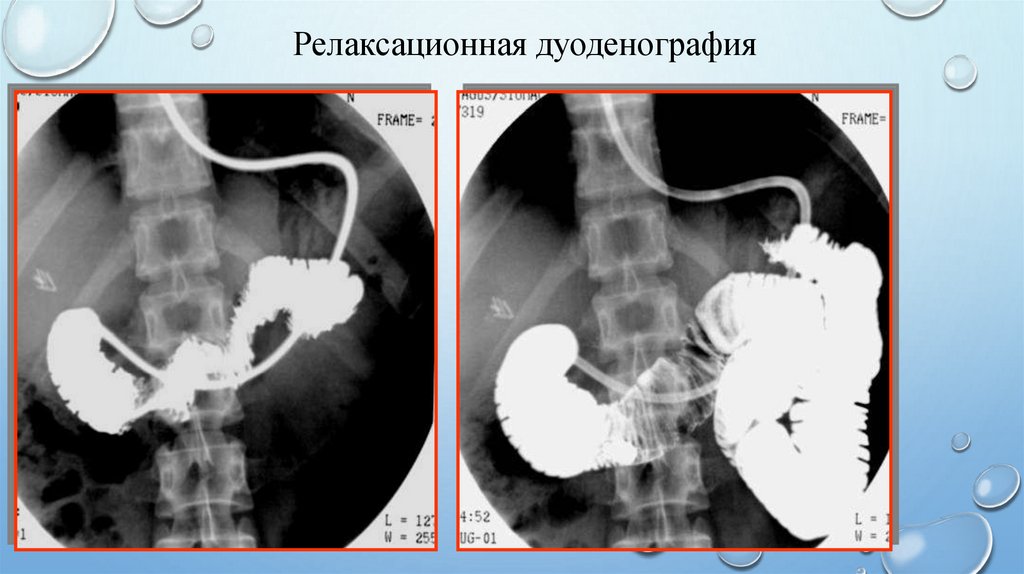

ее гипотонии, вызванной действием

фармакологических средств

Релаксационная дуоденография